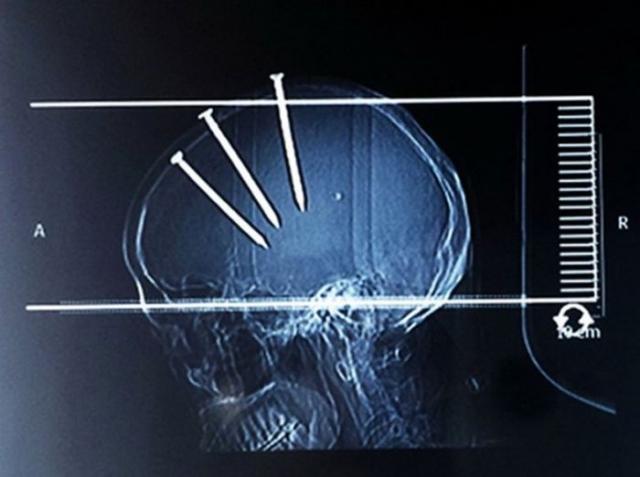

Рентгеновские снимки людей, которые умудрились сами или с чужой помощью разместить внутри своего организма разные посторонние предметы. От вилок и ножей до пуль и бензопилы (!!!). По этическим соображениям обычные снимки таких травм и повреждений выкладывать нельзя, зато рентгеновские можно – на них травмы видны достаточно условно, хоть и очень понятно.